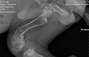

Bingo zabrany ze schroniska w Chełmie 22.11.2023r dnia 26.11.2023 Bingo został przebadany przez dwóch weterynarzy na Browarnej i w Animed gdyż wymiotował krwią i robił kupy z krwią okazało się że postępującą ma parwowirozę nie jadł nie pił był odwodniony wtedy zaczęła się nasza walka o naszego przyjaciela miał podawana surowicę przeszczep kału i założona była sonda Bingus dzielnie walczył do dnia dzisiejszego.Dnia 30.12.2023 dziecko wyszło na spacer z naszym Bingiem obok bloku nikt nie spodziewał się że stanie się krzywda gdyż do dziecka biegł duży pies córka ze strachu wzięła Binga na ręce i nie fortunnie upuściła Binga i dostał złamania kości prawej tylniej niestety RTG potwierdziło złamanie i trzeba przeprowadzić operację to są kolejne koszty leczenia Binga dzięki pomocy ludziom o dobrym sercu i walka i wiara w Binga wygrał z parwowiroza teraz też będziemy walczyć do końca o Bingusia by nie był kaleką wszystkie faktury będą dołączane prosimy o każdy grosz